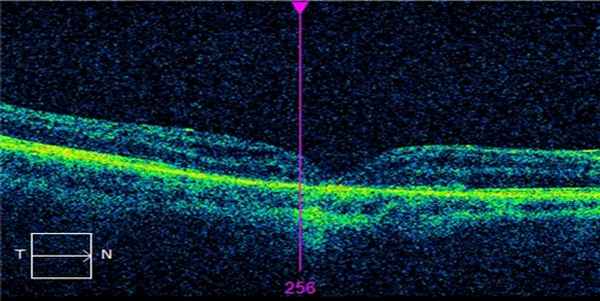

До операции. Макулярный разрыв более 1000мкн.

После операции. Разрыв закрыт.

После операции. ОСТ. Вернулась анатомическая форма фовеа.